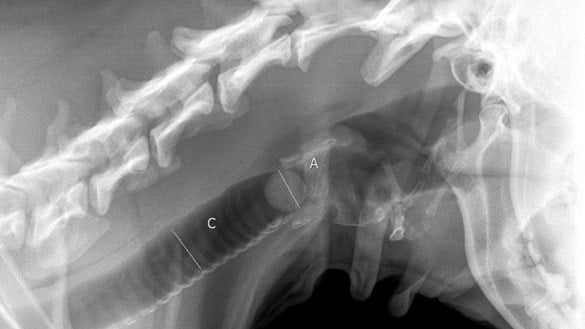

Fudge, a three-year old female dog, was playing in the family home with Maria Napper’s ten-year-old son Archie when she accidentally ate a marble. To the horror of the family, Fudge started to choke right in front of them. Realising the danger, Maria rushed the dog to the Medivet Peterborough Bretton practice on Rightwell East, where she was immediately admitted for emergency treatment. Gasping for air, Fudge started to turn blue. Lead Veterinary Surgeon Pedro swiftly intervened by creating an opening in the neck in order to place a tube into the dog’s windpipe to restore her ability to breathe.

The marble proved too large to extract, so Pedro was forced to operate - extracting the object through her windpipe. The windpipe was repaired and the temporary tracheostomy tube was removed.